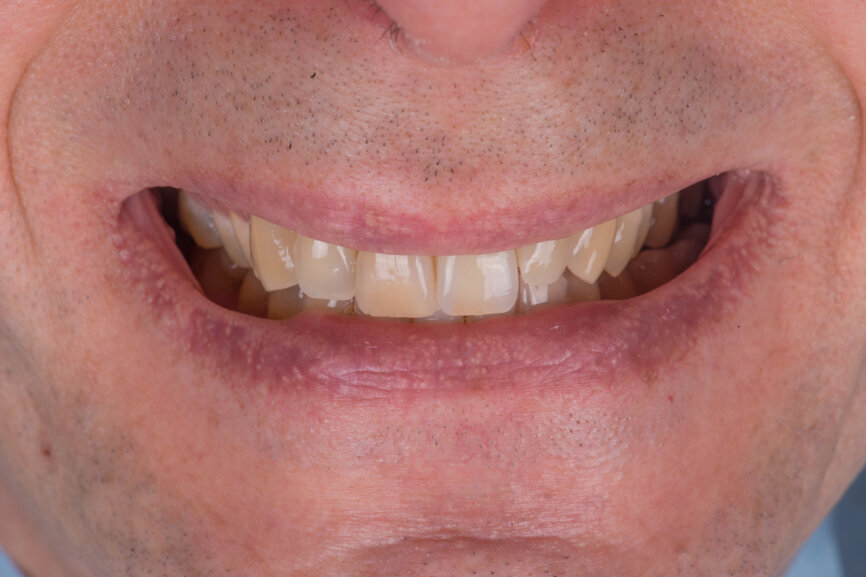

A 52-year-old man, a non-smoker in good general health, was referred after diagnosis of post-traumatic resorption affecting the roots of teeth #11 and #12 (Figs. 1a & 1b). The patient had previously consulted with an endodontist, who stated that both teeth were hopeless and therefore extractions were required. Clinical examination revealed a complete, healthy periodontium around tooth #12 with no sign of infection. At tooth #11, a slight tissue oedema associated with chronic irritation in front of the extensive resorption was observed. The intermaxillary relationship was normal, and the analysis of the smile showed a low smile line (Fig.2). Tooth #21 had been replaced by an implant-supported crown. The previously requested CBCT scan showed that the resorption process was more advanced at tooth #11 (Fig. 3).

Fig 2